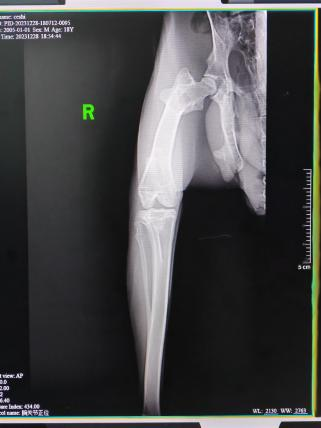

影像学检查

影像学检查:X光、CT、核磁